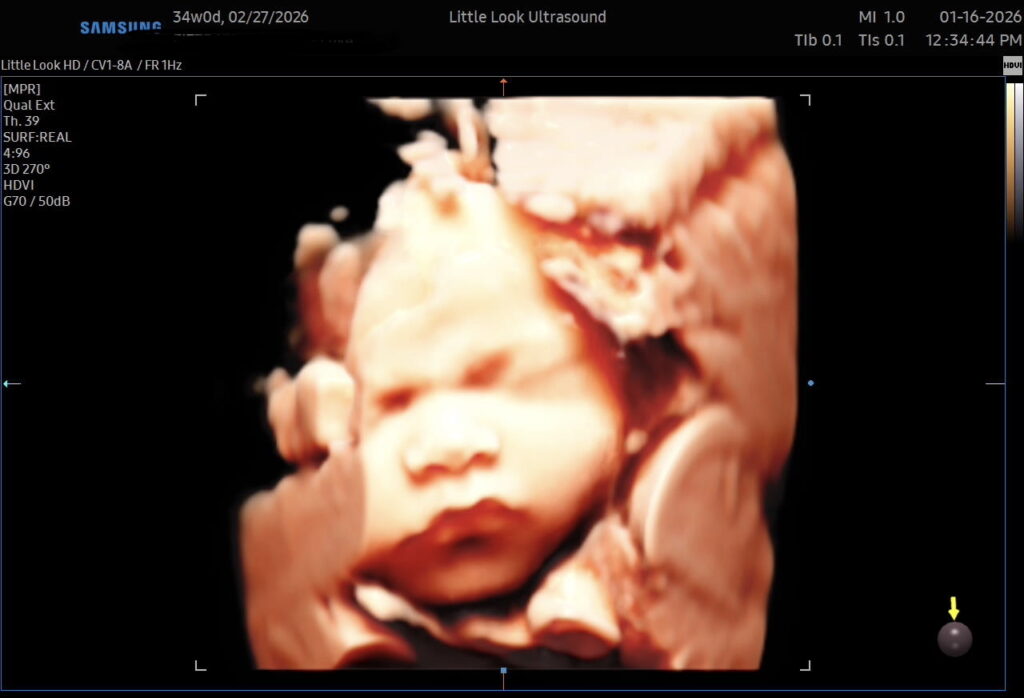

- See your baby’s face in stunning 3D/4D ultrasound imaging

✔️ High-quality 3D & 4D ultrasound imaging